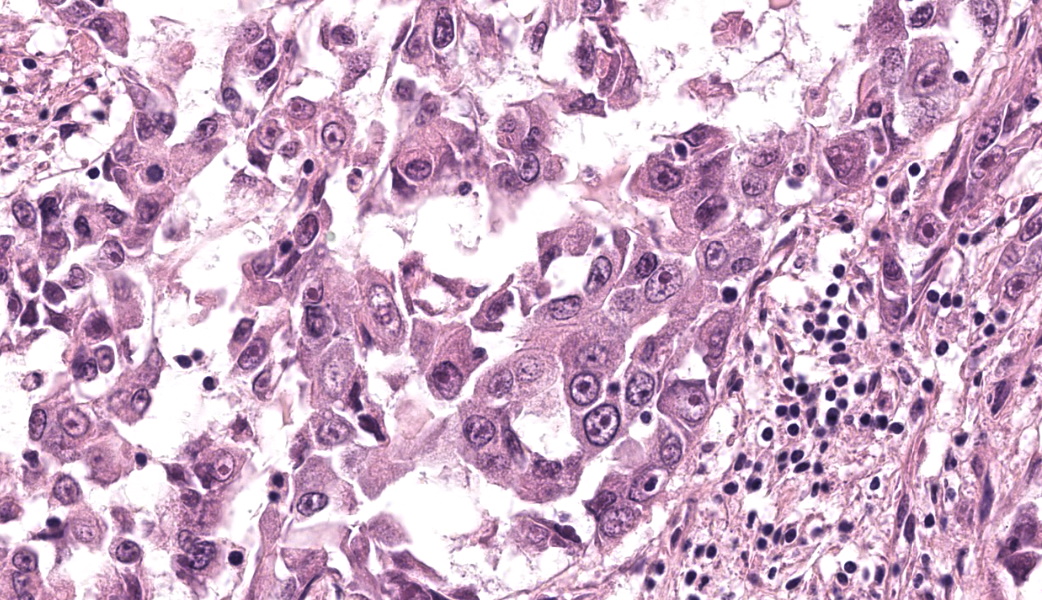

Extending from and infiltrating the omentum is an unencapsulated, poorly demarcated, moderately cellular neoplasm composed of cuboidal to polygonal cells arranged in acini, tubules and nests, and more rarely micropapillary projections, on a moderate fibrovascular stroma. Neoplastic cells have variably distinct cell borders, an abundant amount of granular, eosinophilic and occasionally indistinctly vacuolated cytoplasm, and a pleomorphic, centrally placed nucleus with finely stippled to marginated chromatin and up to 3, occasionally very large distinct magenta nucleoli. There is marked anisocytosis and anisokaryosis, and 21 mitotic figures in 2.37mm2 – equivalent of 10 high power fields (40x obj); these are occasionally bizarre. There are occasional multinucleated neoplastic cells with up to 3 nuclei which occasionally compress and occasional apoptotic bodies are seen. Multifocally, neoplastic stroma contains minimal extravasations of erythrocytes (haemorrhage), and there are multifocal mild infiltrations of deform adjacent nuclei (nuclear molding).

There is occasional single cell necrosis, andmainly mature small lymphocytes, some plasma cells, and fewer neutrophils. Blood vessels are multifocally moderately congested and are often lined by plump (reactive) endothelium.

This third case was challenging due to the epithelioid nature of this mesothelioma. Most conference participants were readily able to reach a diagnosis of “carcinoma” or “adenocarcinoma” and many listed epithelioid mesothelioma as a differential. Tissue identification was challenging and only the most experienced participants felt confident calling it omentum based off the HE secttion. The features described by these participants that clued them in to “omentum” included a nodular “string of pearls” subgross appearance, the composition of a highly vascular fibroadipose tissue, and the wherewithal to remember that the omentum exists in the first place, which can be challenging in and of itself some days. The contributor provided a succinct, eloquent write-up on mesotheliomas and their classifications, which were covered during the conference discussion.

An interesting feature within the nuclei of some of the neoplastic cells caught the eye of a few of the participants. Infrequently, neoplastic mesothelial cells have what look like irregularly shaped, eosinophilic, intranuclear inclusion bodies (INIBs). This is an uncommon, but documented, feature of certain mesotheliomas in humans that can be seen both cytologically and histologically, particularly in adenomatoid and epithelioid forms.5,6 INIBs have also been seen, albeit rarely, in laboratory hamsters and rats infected with SV40 that subsequently developed mesothelioma.21 INIBs are reported, also rarely, in both cattle and dogs with mesothelioma associated with asbestos exposure, although the significance of those inclusions is unknown. Lastly, INIBs can be a rare feature of reactive mesothelial cells as well, making their presence challenging to interpret, but may prompt pathologists to assess for viral or asbestos-related causes.21